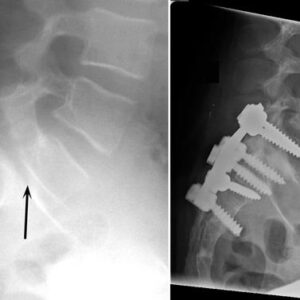

Hand and wrist Patient informationUlnar shortening surgery is a specialized orthopedic procedure aimed at reducing chronic pain on the ulnar (outer) side of the wrist. Performed by experts like Prof. M. Imam, a leading orthopedic surgeon, this operation is commonly recommended for patients experiencing ulnar abutment syndrome or chronic issues with the triangular fibrocartilage